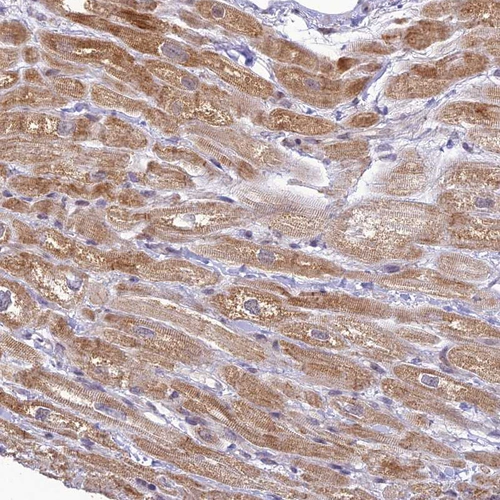

Immunohistochemical staining of human heart muscle shows strong cytoplasm granular positivity in cardiomyocytes.